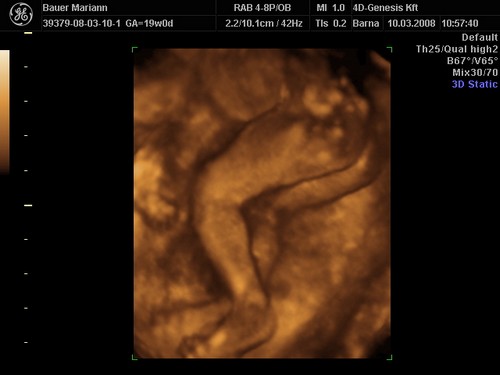

lányok tegnap bevettem egy maltofer vasat és olyan hasmenésem volt most reggel hogy hajjaj ez normális :?: na meg két pici tűszúrásnyi piros pötty lett a pocakomon,jujj megyek mert 10re oda kelll érni a genesisbe látjuk a kicsiket :D jajjj de jó

KépetKépetKépet

Drága picikéim nem voltak túl szereplős hangulatukba úgy kellett kikönyörögni őket a méhlepényből,és még igy sem letek túl élesek a képek.jázmin 266gr ,amy 300gr,jázmin egyszer úgy fejberúgta amyt úgy sajnáltam :D olyan édes formás kiscsajok el vagyok ájulva ,szép egézségesek tele pocakkal,megzabálom őket :D

De nekem eltalálták a 4DGenesisben, nálam tényleg 2 kukis van, igaz, én 2 héttel idősebb terhes voltam, mint te az első 4D-s kukucson.